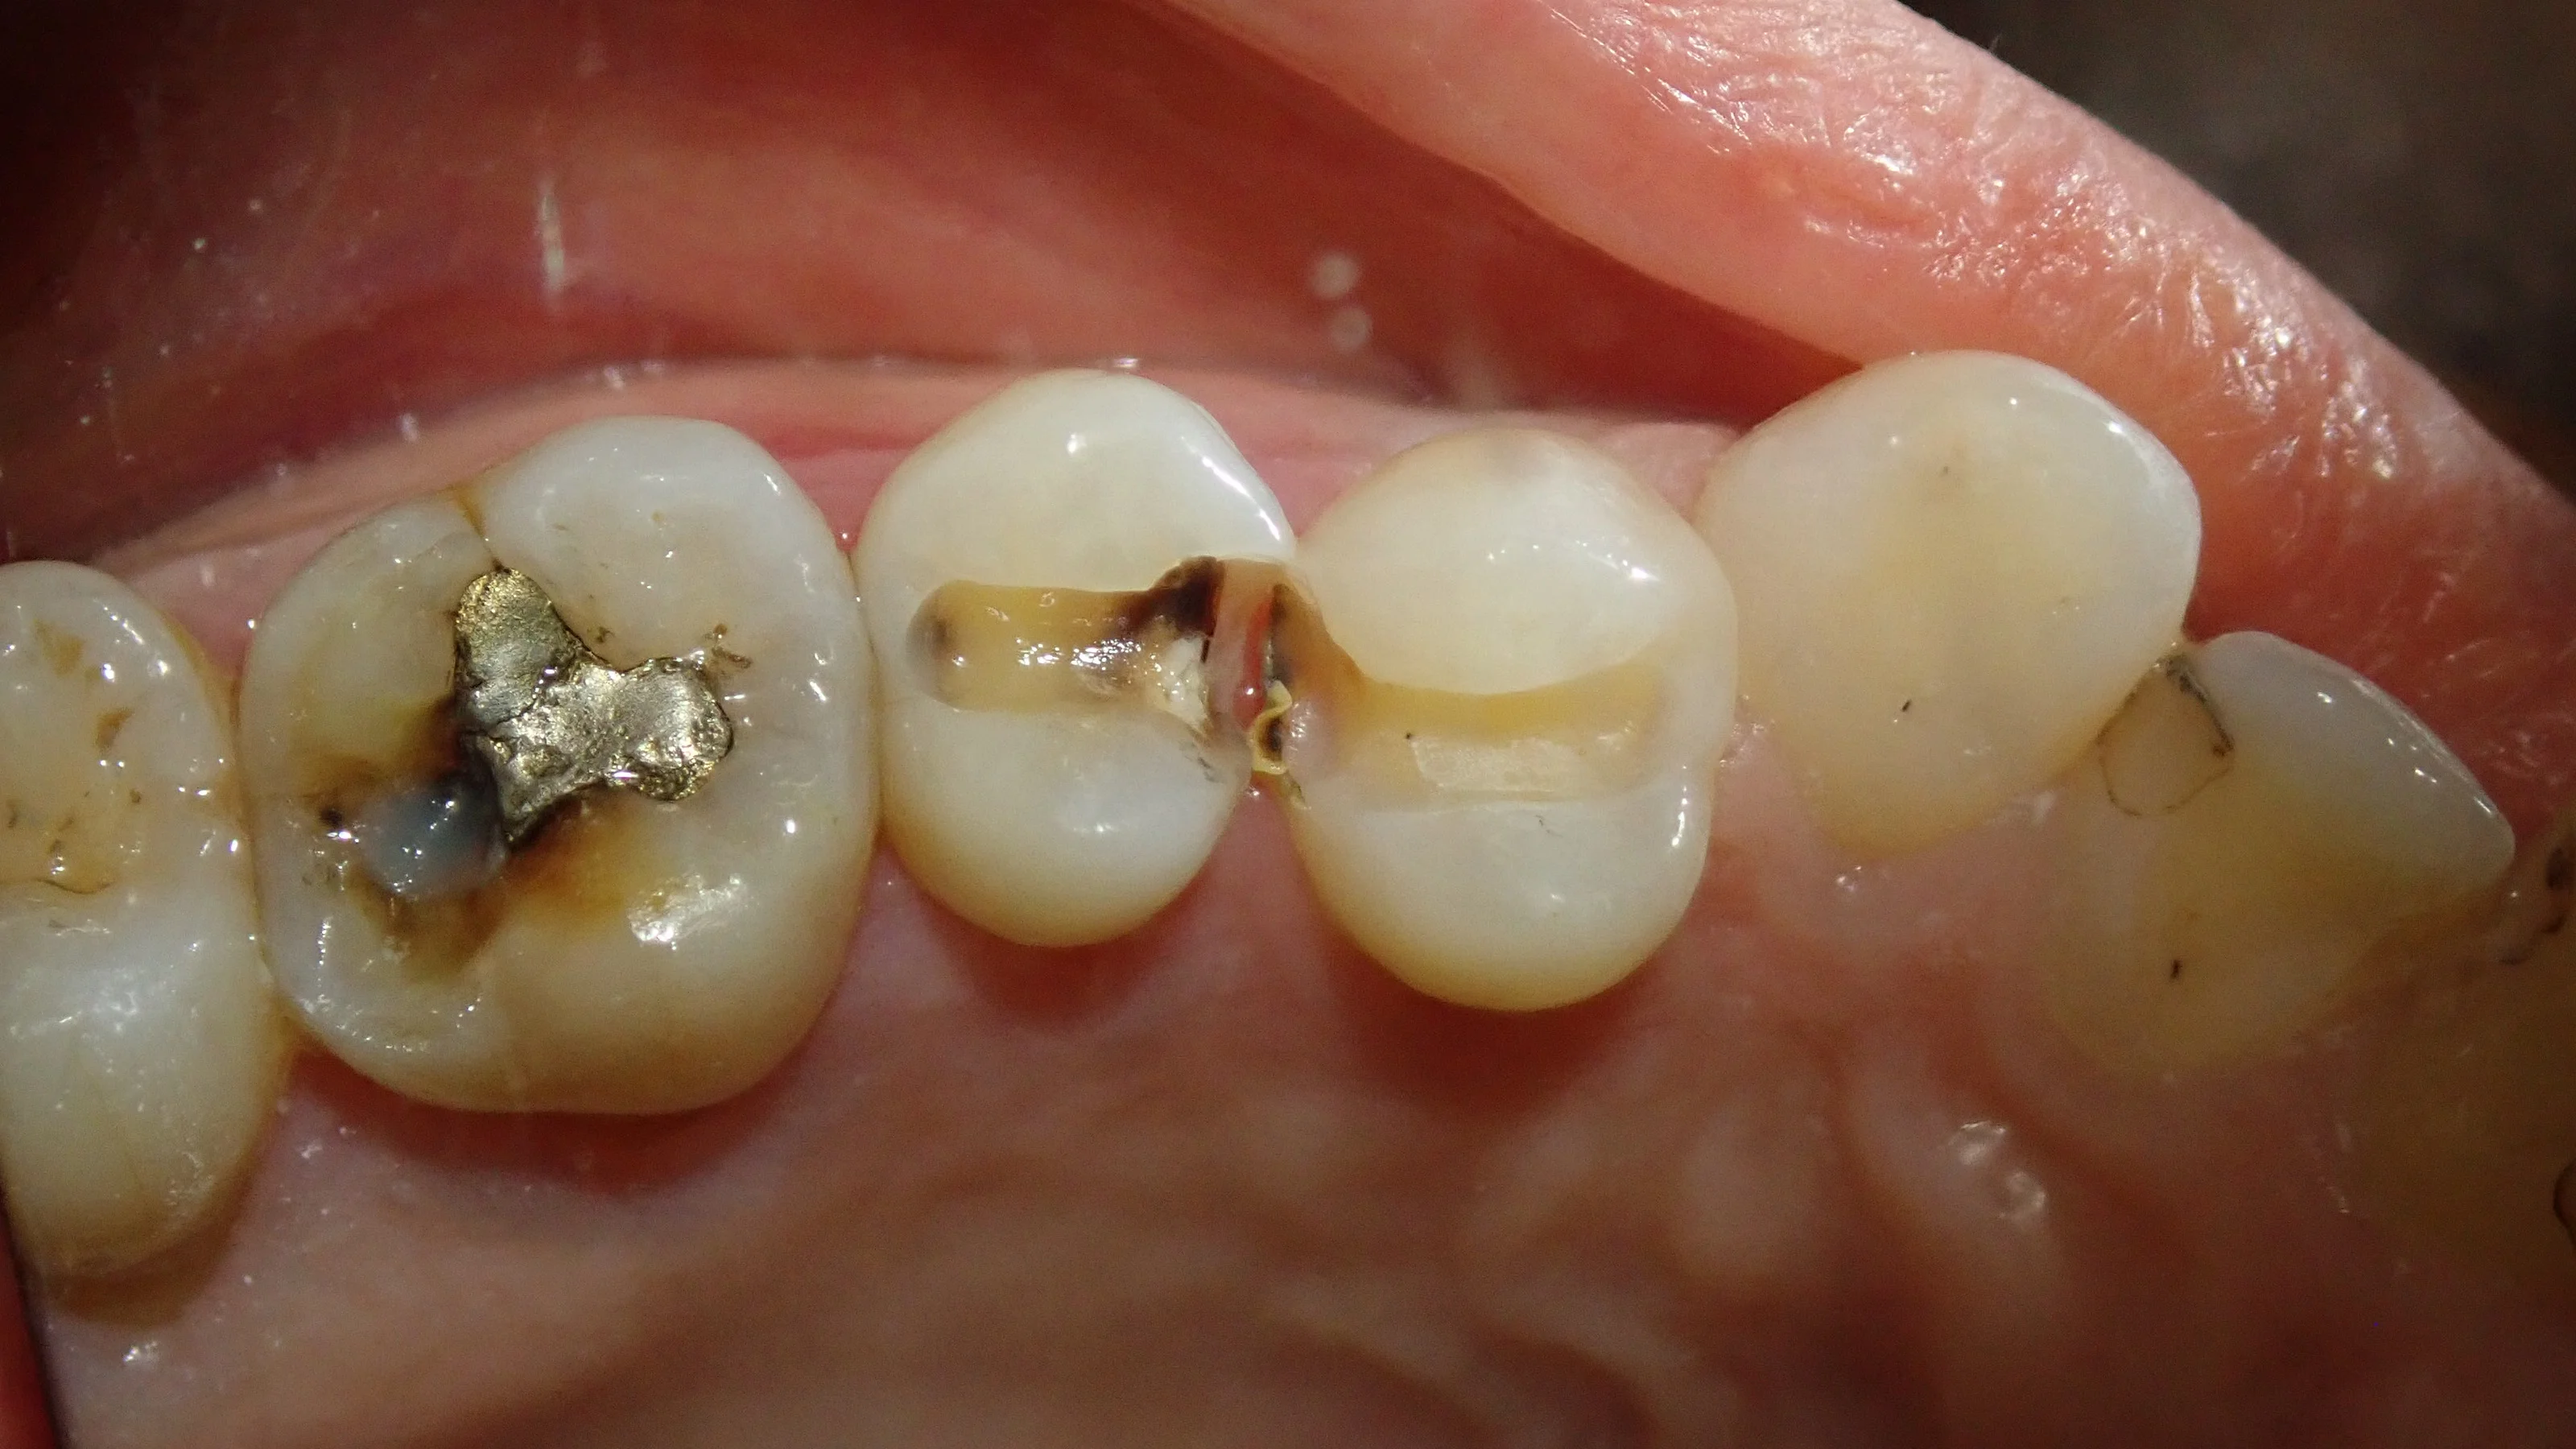

詰め物だけ完全に除去してみると、こうなりました。

左側の歯が、その更に奥の歯との間にも虫歯があることが分かりました。

どうせ費用も手間も変わりませんので、本人にもそのように説明後、そのまま虫歯を全て取り除きました。